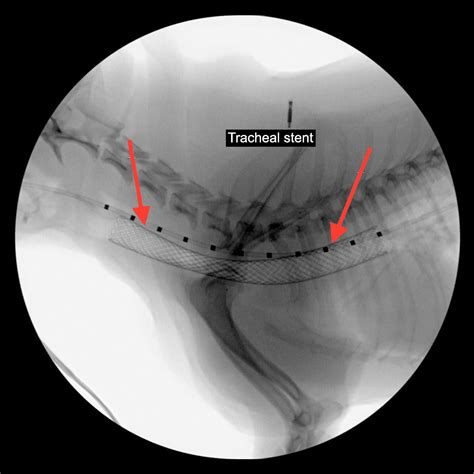

+Diagnosis is typically made through a combination of physical examination, medical history, and diagnostic tests such as radiographs (x-rays) and fluoroscopy.